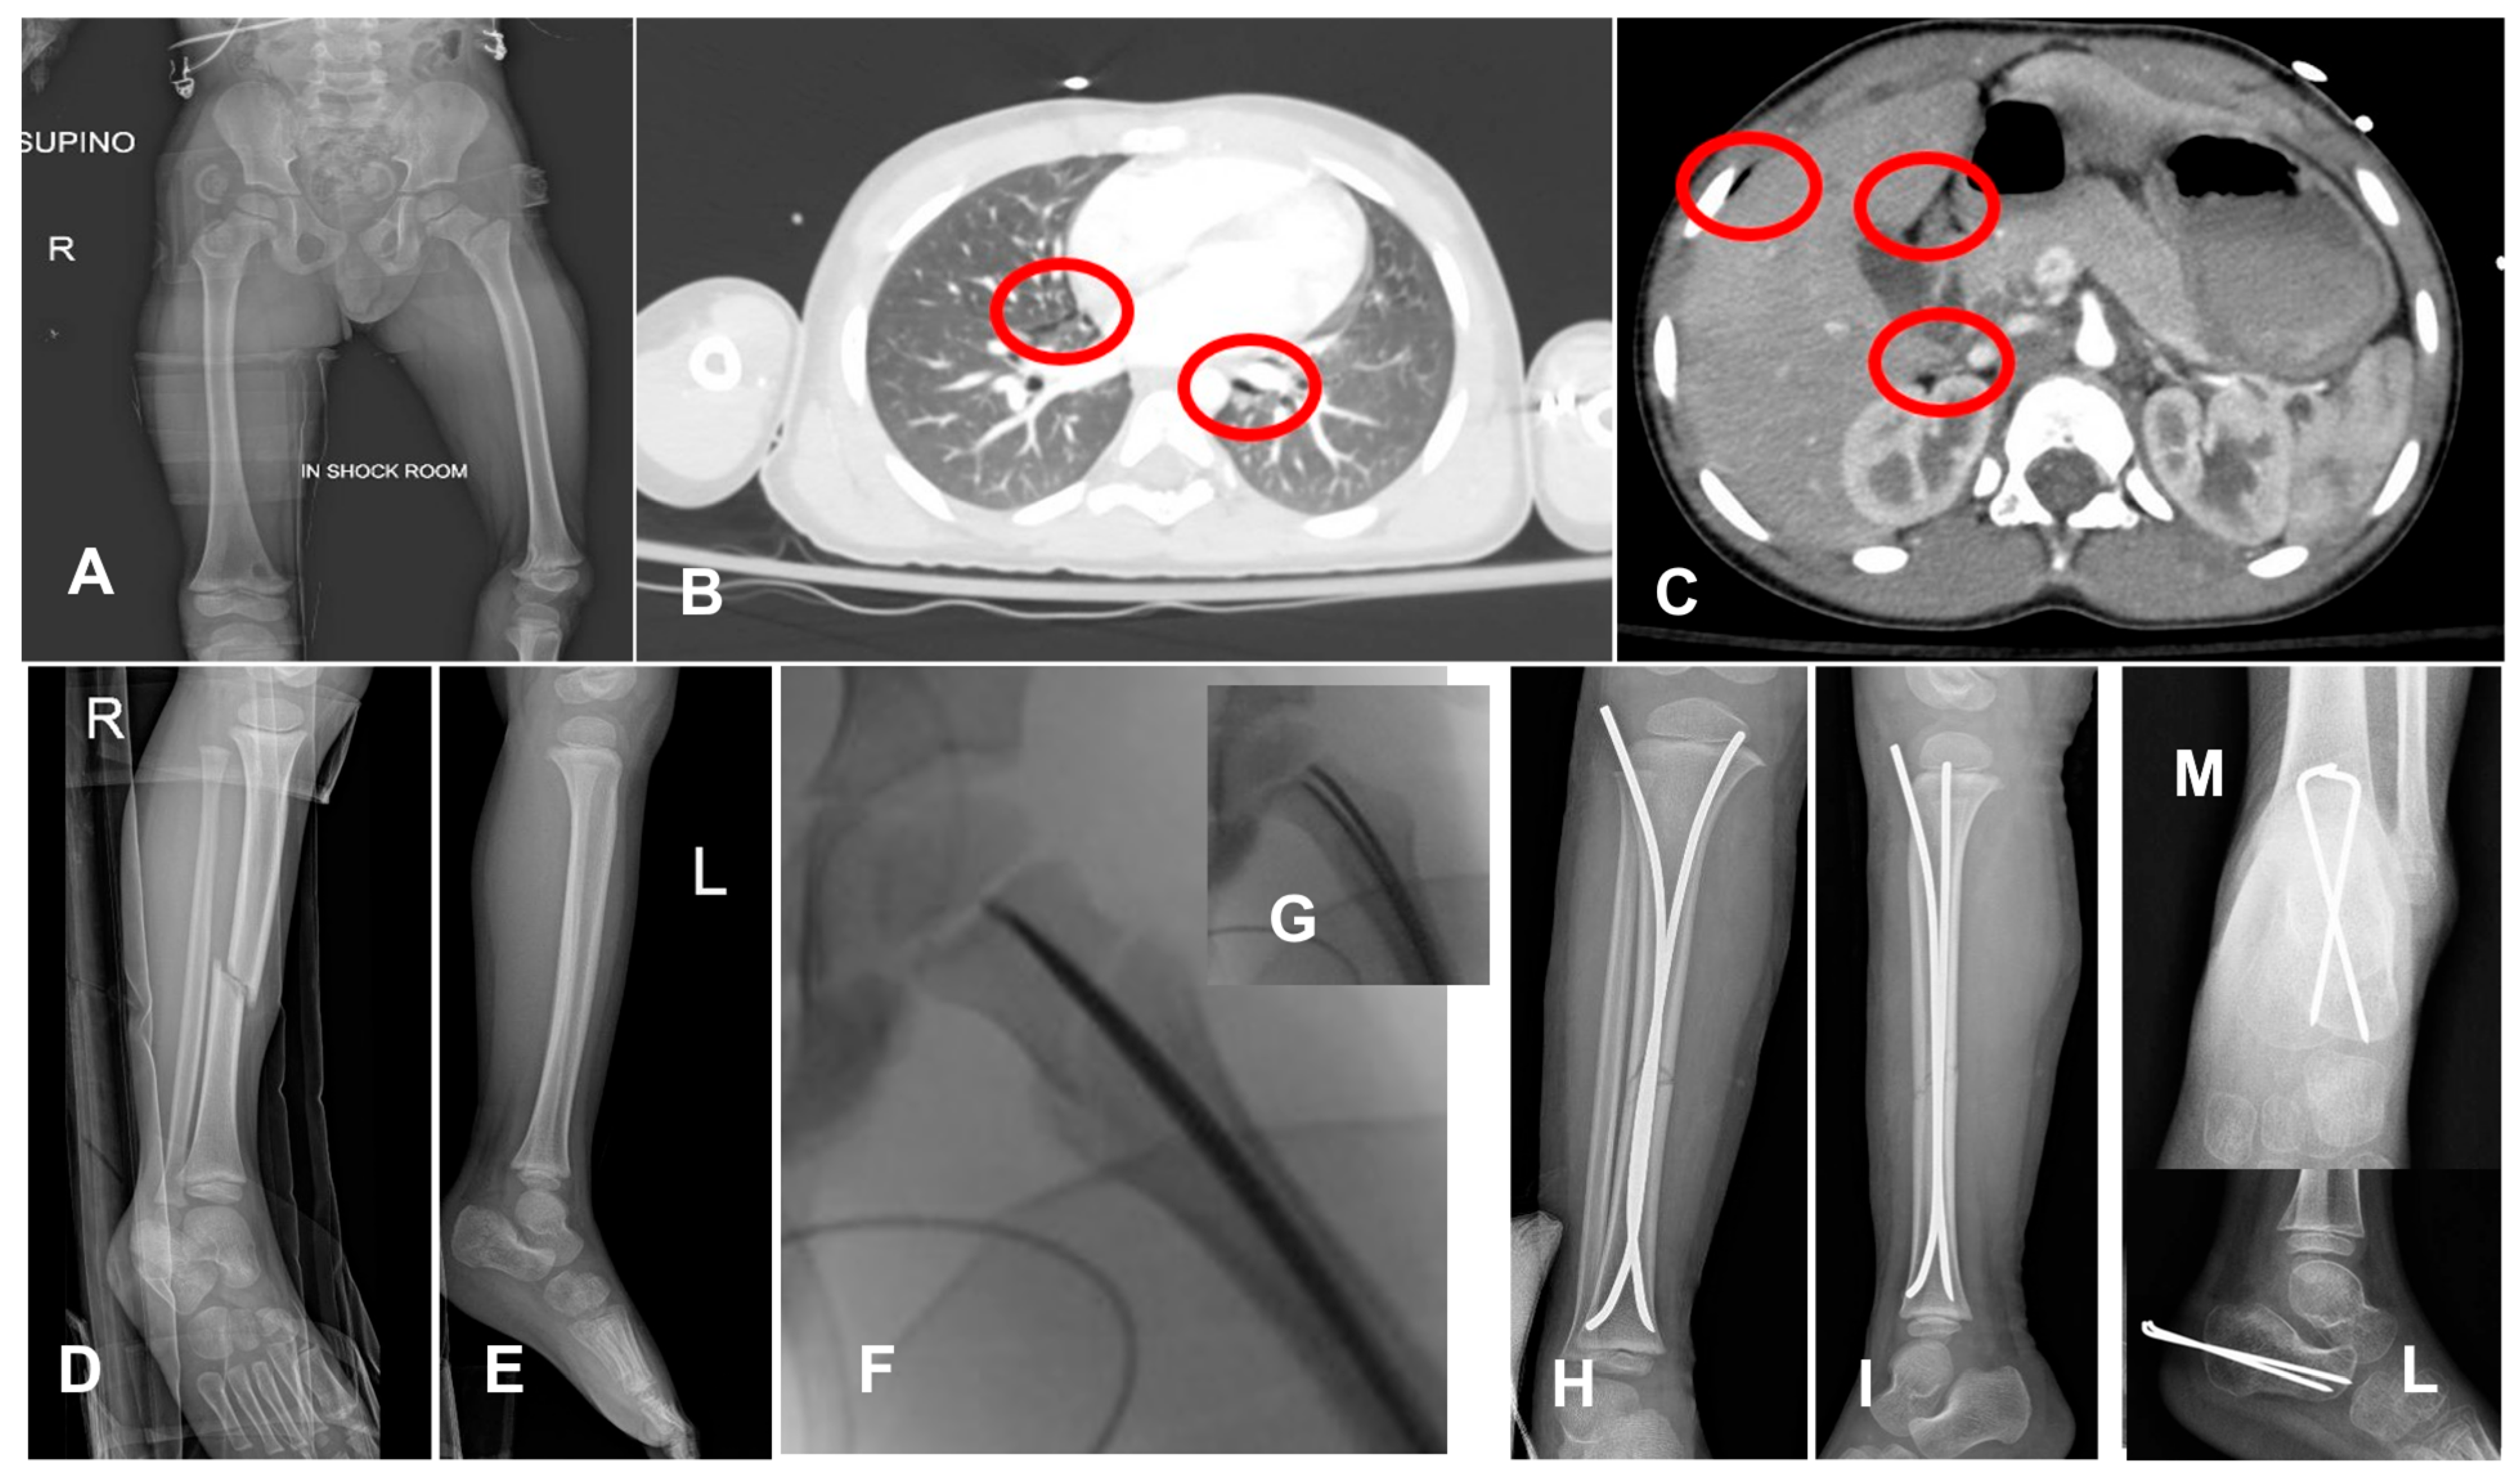

- In the age-group 15–17 years, 23/23 (100%) cases were treated with temporary external fixation (ExFix);

- In the age group 12–14 years, 9/14 (64%) cases were treated with ExFix, and 5/14 (26%) cases were treated with elastic stable intramedullary nails (ESIN);

- In the age group 5–11 years, 1/5 (20%) cases were treated with ExFix, and 4 cases were treated with ESIN;

- In the age group 0–4 years, 2/4 (50%) cases were treated with ESIN, and 2/4 (50%) cases were treated with a hip spica cast.